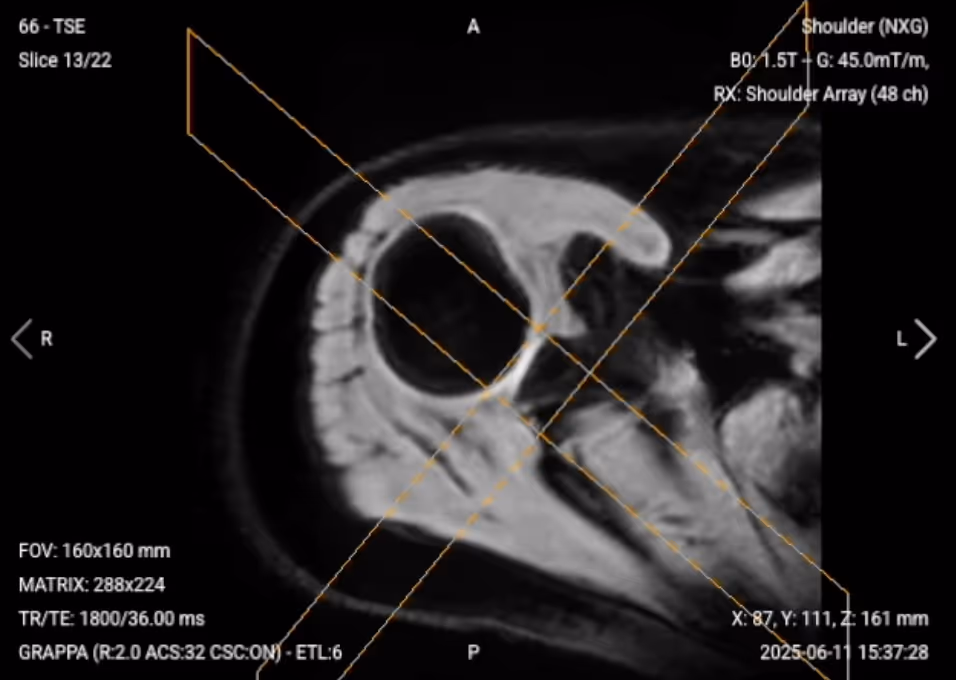

✅ Axial PD FS of the Shoulder – Correct Image Example:

Things to Look for in Axial PD FS: